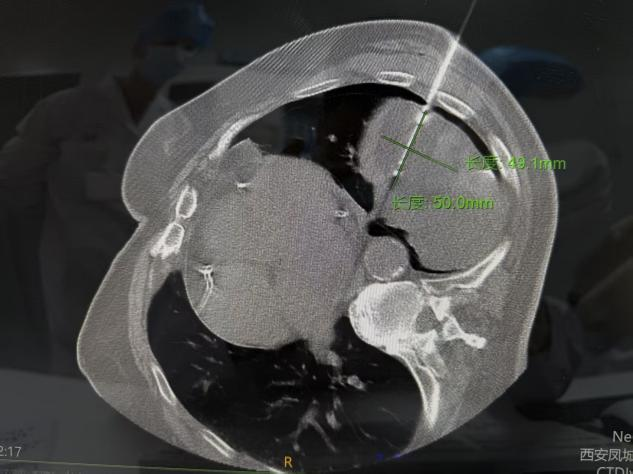

病例二

此次接受手术的两位患者,因身体基础状况、病灶位置等因素,均不适合传统外科手术治疗。胸外科开科后,第一时间组织团队对患者病情进行全面评估,联合医学影像科等科室开展MDT多学科讨论,为两位患者量身定制了个体化冷冻消融治疗方案。手术在局部麻醉下进行,在CT实时精准引导下,将超细冷冻消融针穿刺至病灶核心区域,通过超低温冷冻,精准摧毁病变细胞,同时最大程度保护周边正常组织和重要血管、神经。整个手术过程高效、微创,两位患者术中生命体征平稳,全程保持清醒且痛感轻微,皮肤上仅留针眼大小的创口。术后即刻复查影像显示,消融范围覆盖病灶,达到预期治疗效果。术后患者恢复迅速,2小时内即可下床活动,有效缩短了住院周期,患者及家属对治疗效果和就医体验均表示高度认可并送来锦旗感谢。